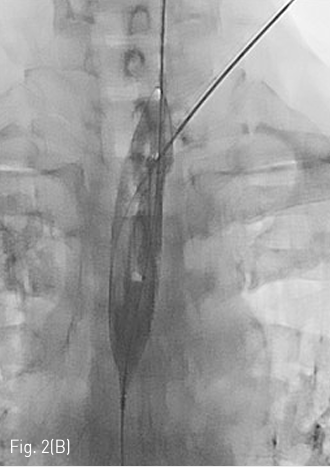

Fluoroscopy 유도하에 경구를 통해 0.035 인치 유도철사 (Glidewire, Terumo, Tokyo, Japan)를 위 속까지 삽입한 후 20mm x 4cm 풍선카테터 (Atlas, BARD, Arizona, USA)를 흉곽입구식도 중간부위에 위치하도록 하였다. 조영제와 생리식염수를 혼합하여 풍선카테터를 팽창시켰고, 초음파 유도하에 팽창된 풍선을 percutaneous transesophageal approach 하여 18게이지 바늘 (Chiba biopsy needle, Cook, Bloomington, USA)로 천자하였다(Fig. 2. A-B). 천자 바늘의 속심을 제거한 후 조영제가 역류되는 것을 확인하였다. J-tip 유도 철사 (J-Tip Glidewire, Terumo, Tokyo, Japan)를 터진 풍선 내로 전진시키고, 터진 풍선과 J-tip 유도철사를 식도하부 혹은 위 안쪽에 위치시킨 후(Fig. 3A) 터진 풍선과 입을 통해 삽입되었던 0.35 인치 유도철사를 제거하고 transesophageal J-tip 유도 철사만 남겨 놓았다. (Fig. 3B) 순차적으로 12Fr, 14Fr dilators (Dilator, Cook, Bloomington, USA)를 이용하여 tract을 확장 시켰다. 18Fr 분리 제거형집(Enteral access dilation system, HALYARD, Alpharetta, USA)을 거치한 뒤 (Fig. 3C) 14Fr 빈천자창냄 카테터(MIC; jejunal feeding tube, HALYARD, Alpharetta, USA)를 십이지장내 세번째 부위까지 진입시키고 분리제거형집을 제거하였다(Fig. 3D). 삽입된 카테터는 목 피부에 봉합하여 고정하고 시술을 종료하였다.

Fig 2B

(B) On fluroscopy, the position of inflated balloon is adjusted between the thoracic inlet and Lt. clavicle. Under US guidance, the Balloon is punctured with an 18 G puncture needle through the left neck.